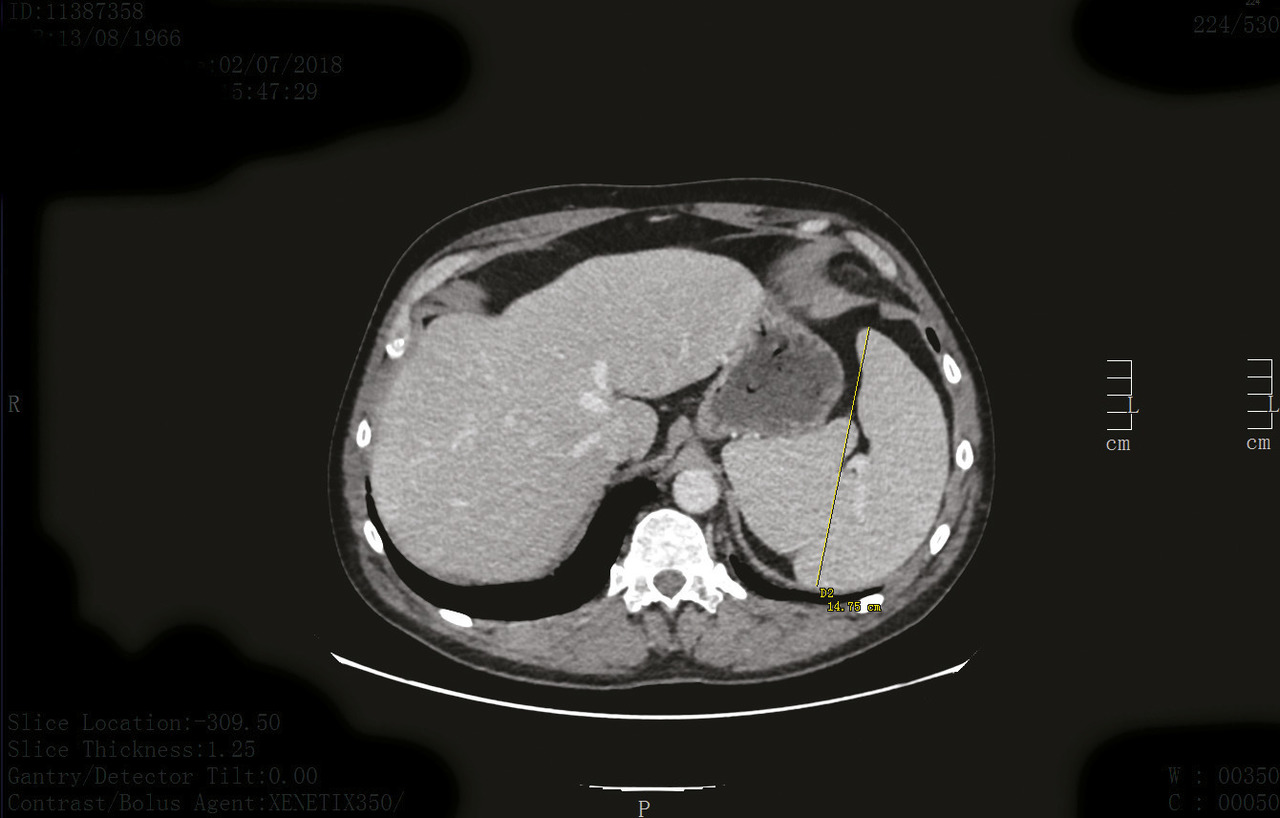

Cet homme de 52 ans, sans antécédent notable, était hospitalisé pour une pneumopathie. Le bilan biologique montrait, outre un syndrome inflammatoire biologique, une pancytopénie prédominant sur la lignée blanche avec une neutropénie à 1 000/mm3, une lymphopénie à 500/mm3 et une monocytopénie entre 0 et 10/mm3. L’évolution de la pneumopathie était favorable sous antibiothérapie. Devant la persistance des cytopénies à distance de l’épisode septique et la présence d’une importante splénomégalie (fig. 1), une relecture attentive du frottis sanguin notait la présence de rares lymphocytes d’aspect « chevelu » (fig. 2). L’immunophénotypage sur sang confirmait le diagnostic de leucémie à tricholeucocytes et un traitement par pentostatine était prescrit (8 cycles de 4 mg/m2).